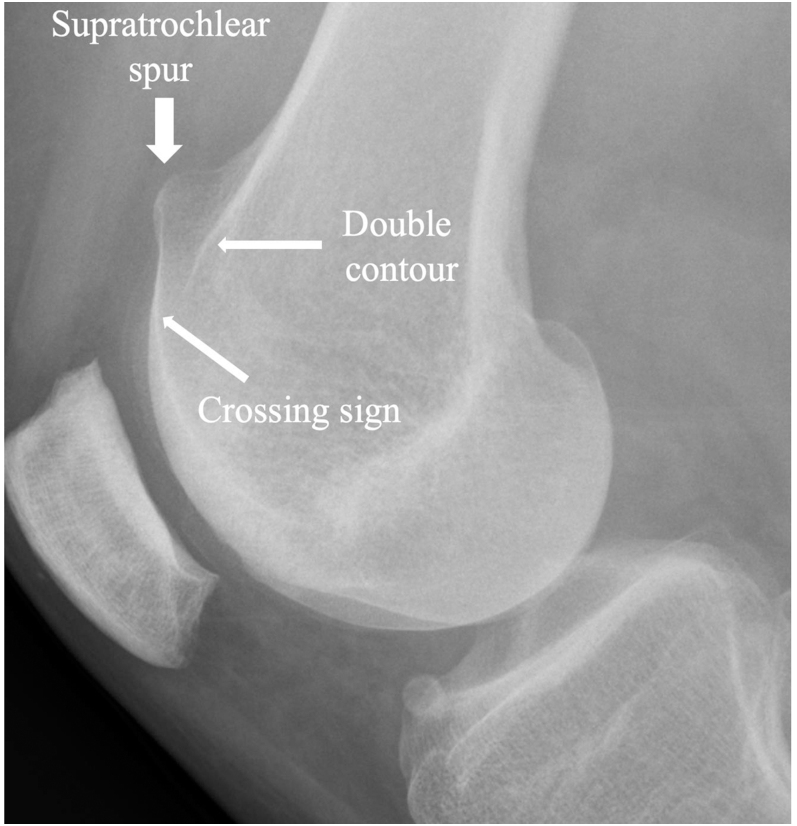

Patellar dislocations present predominantly during adolescence, with a higher incidence observed among female patients. Patellofemoral joint stability depends critically on both osseous anatomy and soft tissue structures. Patellofemoral pathology can be classified into three major groups: objective patellar instability OPI, potential patellar instability and painful patellar syndrome. Three primary risk factors predispose individuals to patellar dislocation: trochlear dysplasia, patella alta and increased tibial tuberosity-trochlear groove (TT-TG) distance. Three secondary risk factors should be considered: femoral and tibial rotational abnormalities and valgus deformity. MRI has become the imaging modality of choice, enabling precise quantification of OPI risk factors in a single imaging examination. The 'menu à la carte' approach guides the treatment of OPI by addressing the most relevant anatomical risk factors for each patient using statistical thresholds.